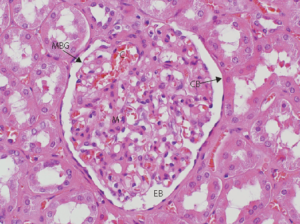

Al microscopio ottico, la malattia è caratterizzata dalla presenza delle semilune, che si formano in seguito alla proliferazione dell'epitelio parietale del glomerulo e alla flogosi concomitante, che porta a un infiltrato di cellule infiammatorie (soprattutto monociti e macrofagi) nello spazio di Bowman. In alcuni casi è possibile osservare proliferazione dell'endotelio o del mesangio.

Al microscopio elettronico si osservano spesso depositi immuni tra l'epitelio e la membrana basale, che in tutti i casi appare colpita da distruzioni focali.

All'immunofluorescenza si possono trovare aspetti diversi a seconda dell'eziologia: nei casi postinfettivi si osservano depositi immuni granulari, nelle forme da anticorpi anti-MBG (sindrome di Goodpasture) i depositi sono lineari, mentre nei casi idiopatici o associati a vasculite i depositi sono spesso assenti.

Con il tempo le cellule che formano le semilune tendono ad essere sostituite da tessuto fibroso.